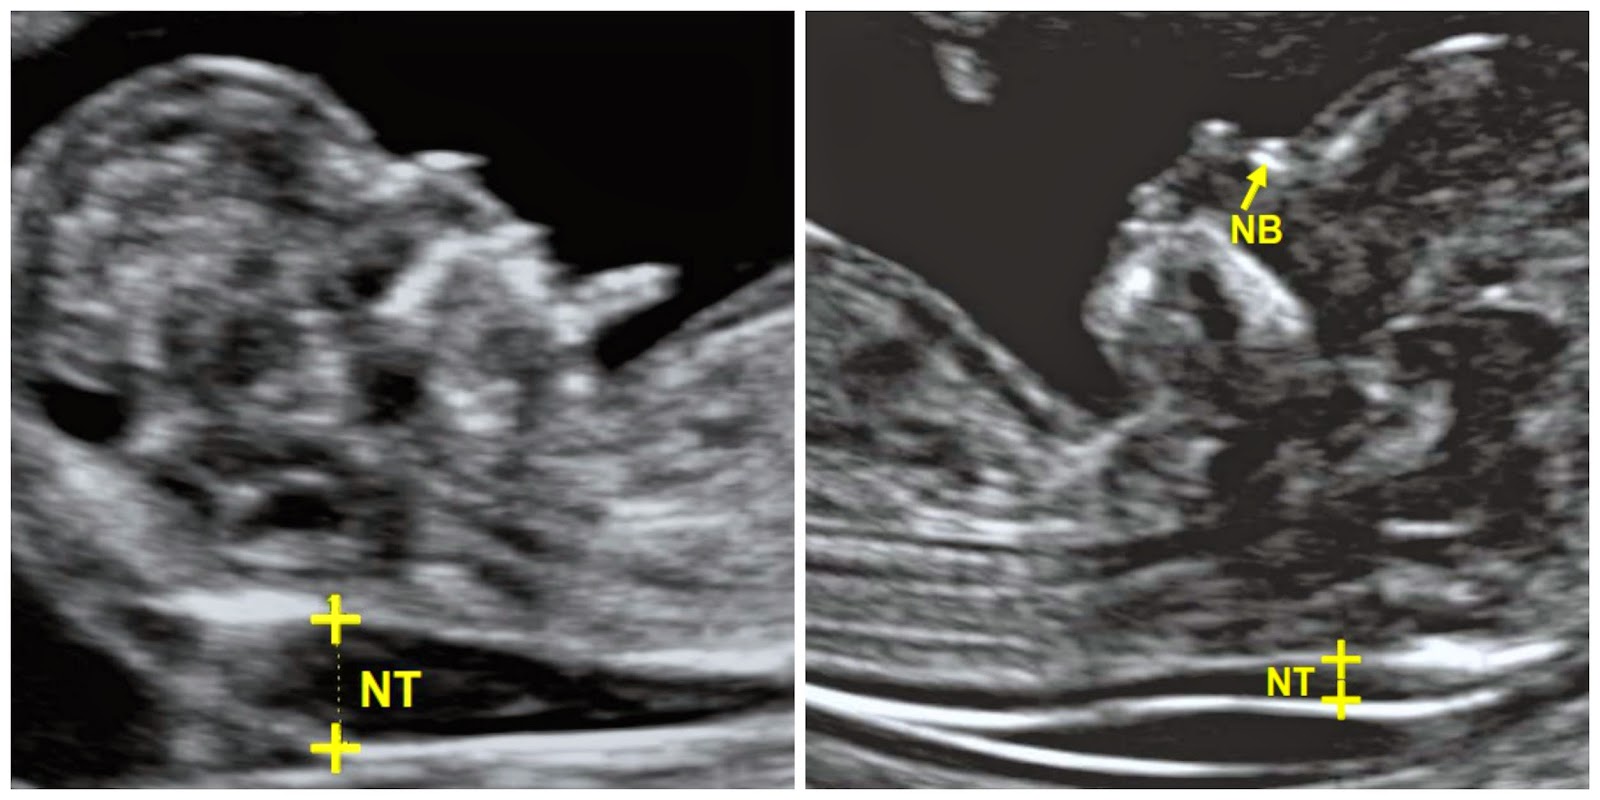

La trisomía 21 completa es la causa de aproximadamente el 95% de los casos de síndrome de Down. 1, 2, 3. Trisomía 21 mosaico. Las células del cuerpo no son exactamente iguales. En alrededor del 1% de los casos de síndrome de Down, la mayoría de las células del cuerpo tienen el cromosoma extra, pero algunas no lo tienen.. La prueba de translucencia de la nuca fetal debe realizarse cuando te encuentras entre las semanas 11 y 14 de embarazo, ya que en esa etapa es cuando la base del cuello del bebé es aún transparente (el último día en que puedes hacerte la prueba es cuando cumples 13 semanas y 6 días de embarazo). En Estados Unidos, esta prueba suele.